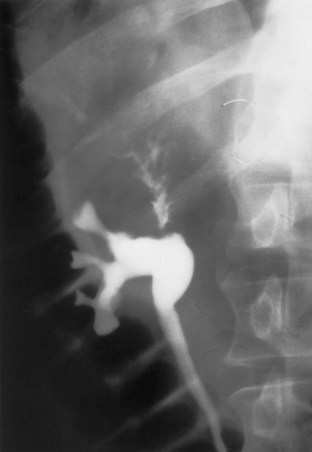

Radiolucent, noncalcified lesions may require additional evaluation by retrograde urography or ureteroscopy, with or without biopsy and cytology. Overall, retrograde urography has an accuracy of 75% in diagnosis of an upper tract malignant neoplasm (Murphy et al, 1981). An incompletely filled or obstructed renal infundibulum or calyx, occurring in 10% to 30% of cases, again typically requires retrograde urography or ureteroscopy to confirm the diagnosis. Obstruction of the urinary tract is a poor prognostic sign for tumor invasion (Babaian and Johnson, 1980).

Even if a voided cytology specimen is abnormal in a patient with an upper tract filling defect, one must be cautious in determining the site of origin of the malignant cells. Ureteral catheterization for collection of urine or washings may provide more accurate cytologic results. However, even in this setting, a substantial false-negative or false-positive result (22% to 35%) can be expected (Zincke et al, 1976). It would appear that saline washing provides a better cell yield and improves cytologic results secondary to the release by hydroscopic forces of loosely adherent cells from the urothelium. Still better accuracy can be achieved by brush biopsy through a retrograde catheter or ureteroscope. Sensitivity in the 90% range with specificity approaching 90% may be possible with these techniques (Streem et al, 1986; Blute et al, 1989). Brush biopsies have, however, also been reported to result in severe complications, including massive hemorrhage and perforation of the urinary tract with extravasation (Blute et al, 1981).

It appears that the exposure of urothelial cells to ionic, high-osmolar contrast agents as in retrograde pyelography may worsen cytologic abnormalities. Thus, it is probably prudent to obtain cytologic specimens before the use of these agents (Terris, 2004).